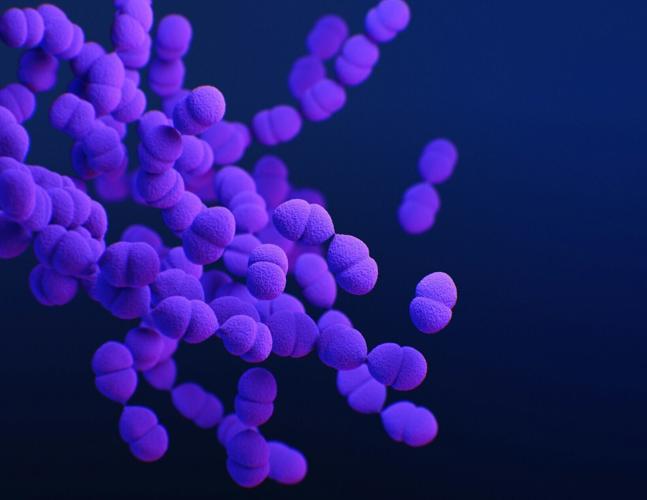

CDC